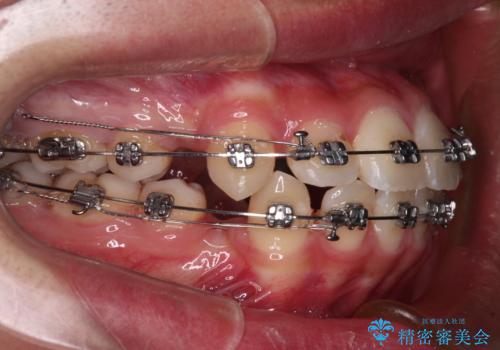

- 矯正装置

- メタルブラケット

上下前歯がくちばしのように突出していたため、上下左右の第一小臼歯4本を抜歯し、ワイヤー装置にて矯正治療を行うこととしました。

左上は第二小臼歯が90度捻れており、状態が良くない歯であったため、左のみ第二小臼歯を抜歯することとしました。

第二小臼歯抜歯により治療期間が長くなることを了承いただき、治療を開始しました。